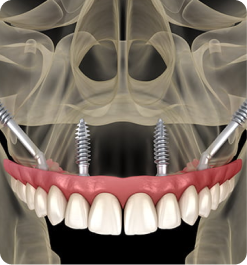

CREDENCIAMENTO EM FIXAÇÕES ZIGOMÁTICAS E APERFEIÇOAMENTO NAS TÉCNICAS ALL ON FOUR

Coordenação: Paulo Abdalla Saad

• Prática clínica em pacientes!

IMERSÃO NA TÉCNICA ALL-ON-FOUR

Coordenação: Dr. Marcelo Zamperlini

Público alvo: Cirurgiões dentistas Implantodontistas, Periodontistas e Bucomaxilofaciais.

Curso prático de 3 dias | Material Incluso para todas as Práticas.

IMERSÃO ZIGOMA DAY

Coordenação: Dr. Marcelo Zamperlini

Público alvo: Cirurgiões dentistas Implantodontistas, Periodontistas e Bucomaxilofaciais.

Curso prático de 3 dias | Material Incluso para todas as Práticas.